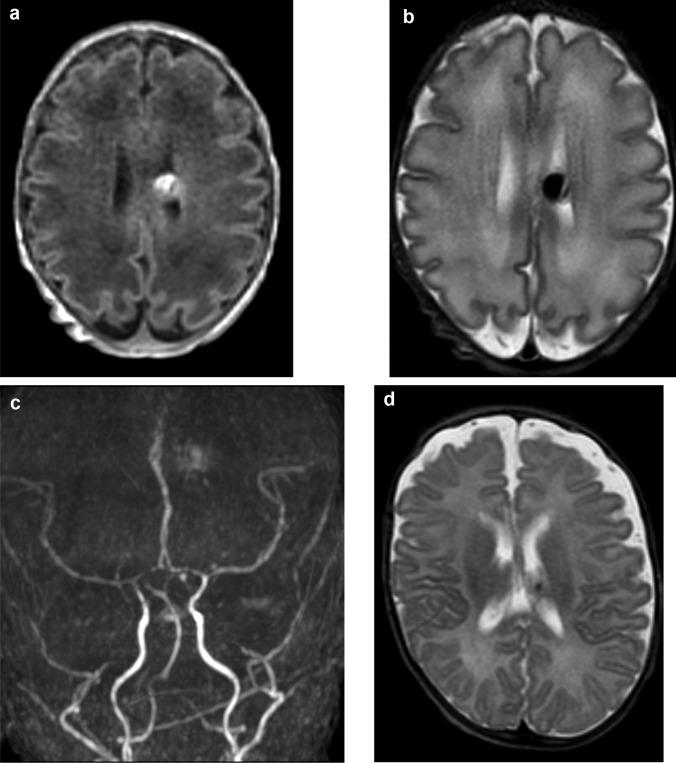

We report a case of an asymptomatic preterm newborn incidentally diagnosed with pAVF during a routine cranial ultrasound (cUS) on the third day of life. Cerebral magnetic resonance (MRI) confirmed the diagnosis. A wait-and-see approach was chosen by the multidisciplinary team. The cUS and the MRI on day 14 of life showed the spontaneous resolution of the lesion.

我们报告了一例无症状早产儿病例,该患儿在生后第 3 天行常规头颅超声(cUS)时偶然被诊断为 pAVF。脑磁共振(MRI)证实了该诊断。多学科团队选择了等待观察的方法。在生后第 14 天行 cUS 和 MRI 显示病变自发消退。